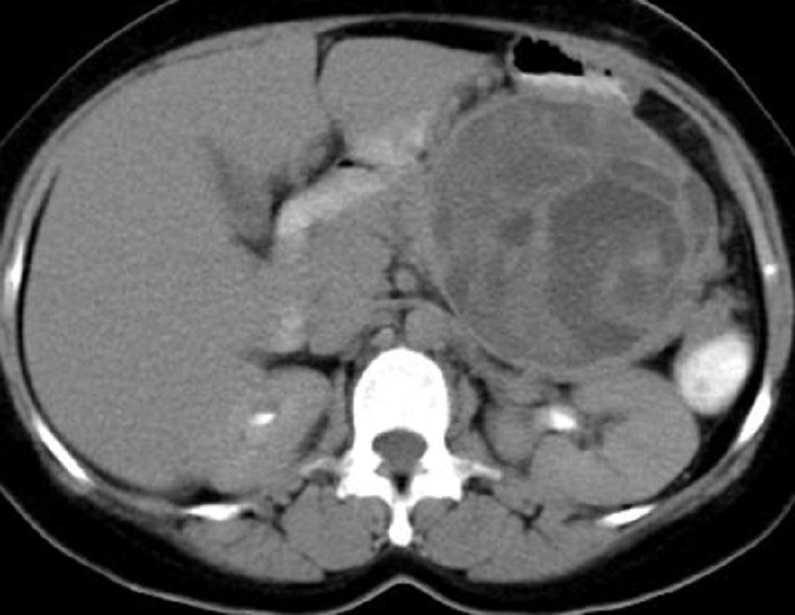

Image radiologique TDM d'une

cystadenome sereux multikystique cephalique du

pancreas a aspect multikystique comporte de plusieur

kyste hypodensite de < 2cm situe a la tete du

pancreas ( fleche rouge ) . Coupe TDM axcilaire |